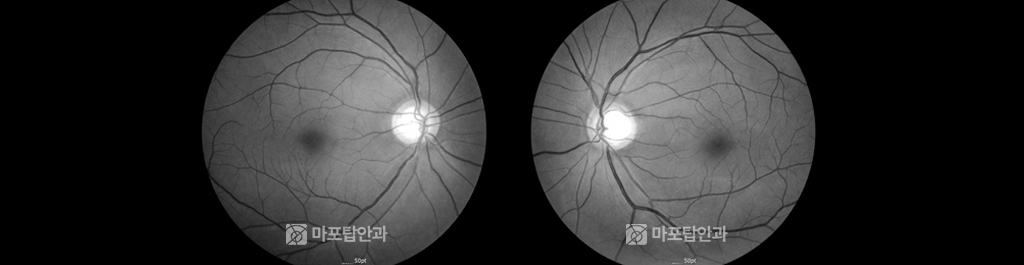

라식 예정이었던 34세 여자 환자의 안저 검진 사진입니다. 좌측 녹내장 의증으로 의뢰되었지만 시야 검사를 비롯한 정밀검사와 논문게재 방법을 이용하여 SSOH(시신경 부분 형성 부전) 정상 진단으로 판정했습니다. 진단 후 7년동안 시신경 섬유의 변화가 없었으며 라식 수술을 진행한 케이스입니다.

유사한 증례로 녹내장이라 진단 받았지만 SSOH로 진단, 경과 관찰 중 시신경 섬유에 변화가 없다는 것을 확인하여 정상 진단으로 판정했습니다.